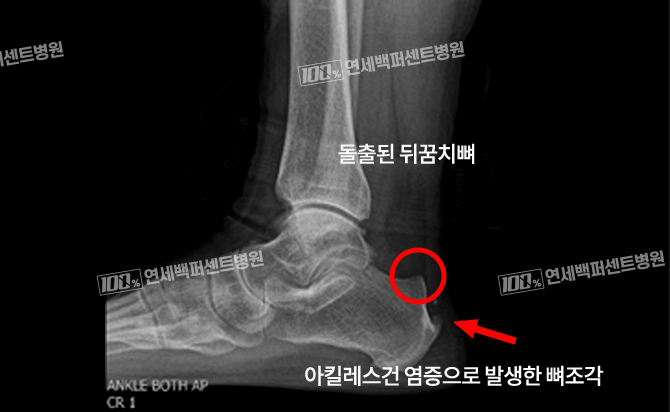

최소침습 해글런드 변형 절제술

긴 절개 없이 최소침습으로 치료!

돌출된 뒤꿈치 뼈와 아킬레스건 염증 동시 치료!

수 차례의 충격파 치료, 주사치료에 반응 없는 난치성 아킬레스건염 해결!

손OO (23.01.09)

손OO (23.03.09)